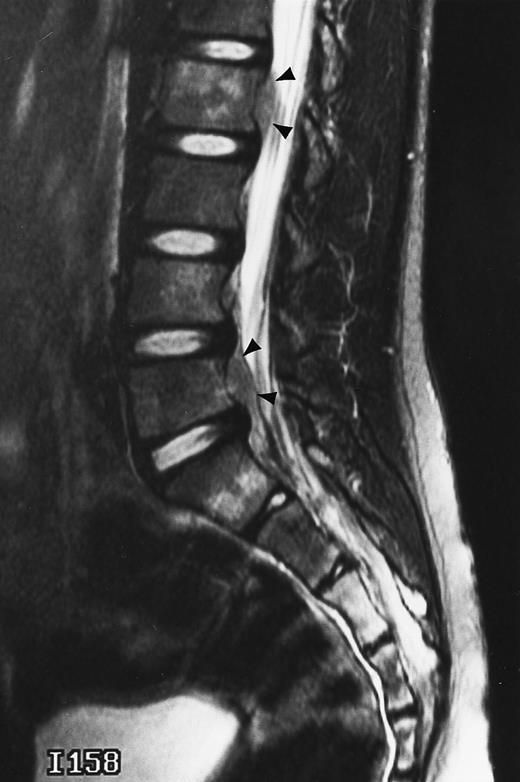

T1-weighted (500/11, TR/TE) sagittal MR images of the lumbosacral spine in a 45-year-old woman before (A) and 40 days after (B) bone marrow transplantation for multiple myeloma. There is a diffuse MR pattern of marrow involvement in (A) (bone marrow plasma cells, 50%; monoclonal protein, 6.0 g/dL). On the posttreatment image, there is definite reinstitution of fatty marrow in the spine and, in particular, around the basivertebral veins, in keeping with partial response to treatment (bone marrow plasma cells, 0.5%; monoclonal protein, 1.6 g/dL).

During the first posttransplantation days, marrow necrosis is seen as a decrease in the signal intensity of the marrow on T1-weighted images and as increased brightness on T2-weighted images. Within 3 months from bone marrow transplantation, a characteristic band pattern appears on T1-weighted MR images of the spine.90 This band pattern consists of a peripheral zone of dark signal and a central zone of bright signal. At histologic examination, the peripheral zone corresponded to repopulating hematopoietic marrow and the central zone to marrow fat.90 Stevens et al90 observed the band pattern in all but 1 of 15 patients within 90 days after bone marrow transplantation and up to a follow-up of 14 months. In 1 patient with relapse of disease, the band pattern evolved to a more homogeneous appearance of the marrow. In our experience, the band pattern gradually evolves into a homogeneous appearance of the marrow after successful bone marrow transplantation.